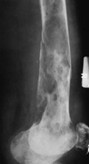

Figure 1: X-rays may demonstrate poorly defined areas of bone loss, appearing “moth-eaten” or mottled.